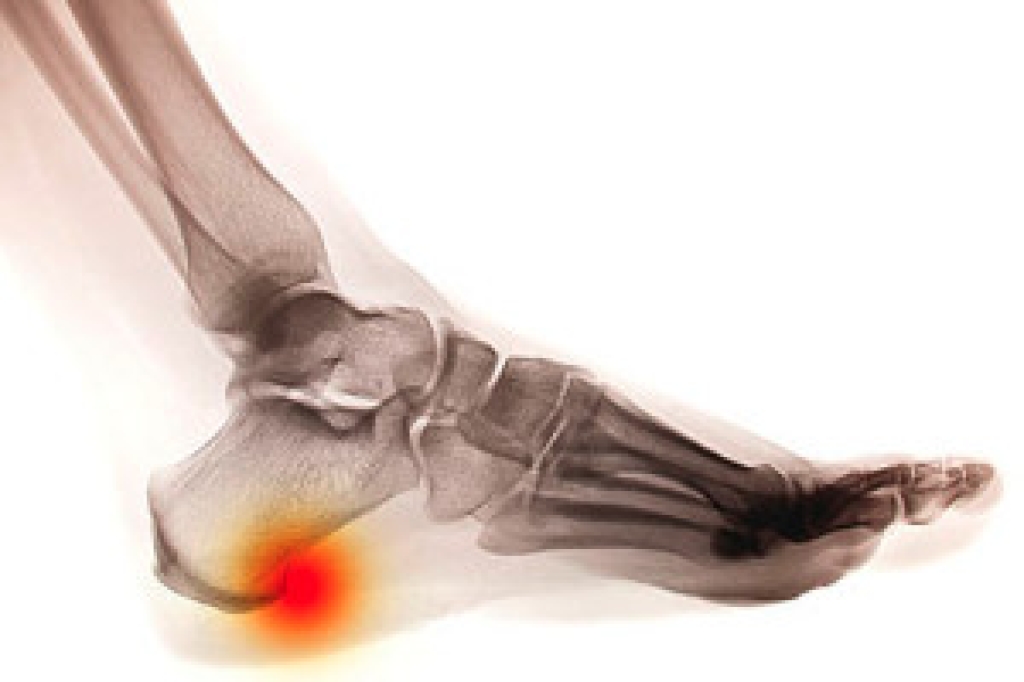

If a calcium deposit should forms between the arch of your foot and your heel, you may have a heel spur. This protrusion may grow gradually, and can be have a hooked, pointed, or even "shelf-like" appearance. Symptoms associated with this condition may include swelling, sharp pains in the heel and surrounding areas, or tenderness that is felt under the heel. If muscle and ligament strain damage the soft tissue in the heel, the result may the formation of a heel spur. Additionally, as the aging process occurs, the heel pads may not provide adequate shock absorption. The symptoms of heel spurs may be similar to those of plantar fasciitis, so it is advised to seek the counsel of a podiatrist who can properly diagnosis this condition.

Heel spurs are formed by calcium deposits on the back of the foot where the heel is. This can also be caused by small fragments of bone breaking off one section of the foot, attaching onto the back of the foot. Heel spurs can also be bone growth on the back of the foot and may grow in the direction of the arch of the foot.